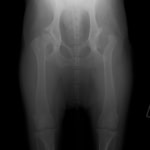

術前レントゲン

術後レントゲン

症例2 ゴールデン・レトリバー 7歳 雌 (石神井病院症例)

ボール遊びの後の後肢の跛行を主訴に来院されました。院内ではモンローウォーク(腰を振って歩く歩様)が認められました。レントゲン検査において、左右股関節の形成不全および比較的重度の関節炎所見を認めました。左右ともに長期に及ぶ骨関節炎の進行により、寛骨臼に重度の骨変形・骨硬化が認められました。このような症例においては、THRのカップの定着が悪くTHRの手術の成功率が下がるため、機能回復の面では劣りますが、症状がより重く、筋肉の萎縮の認められた右後肢の大腿骨頭・骨頚切除術を実施しました。関節面に関節軟骨の欠損、骨増殖体を認めました。今後は、リハビリテーションを行い、患肢の機能回復に努め、反対側の大腿骨頭・骨頚切除術を検討していく予定です。

股関節形成不全は成長期に発症する進行性の関節疾患です。中齢期以前のTHRの実施が機能回復において最も優れています。好発犬種の大型犬は成長期からの定期的な股関節のレントゲン検査をお勧めいたします。(詳しくは上記の診断を参照してください。)